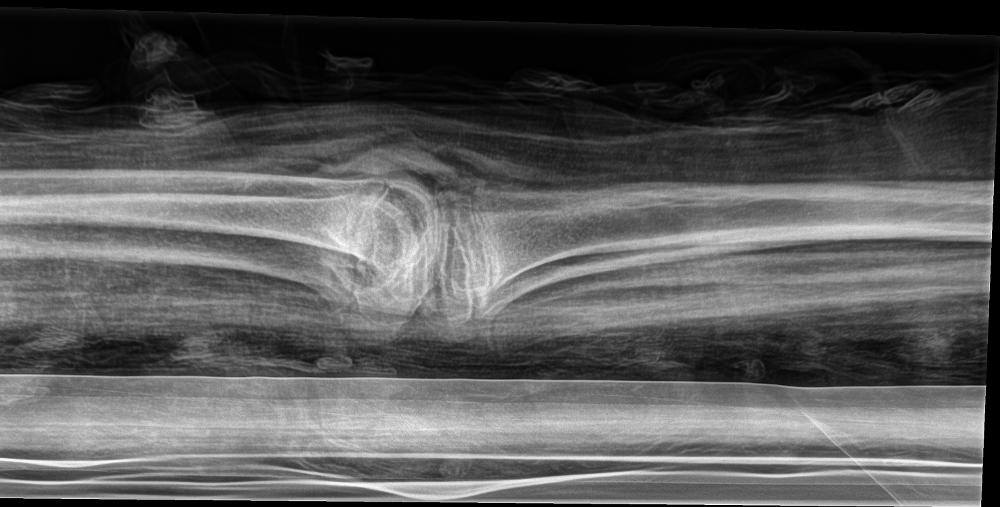

mummy, boy, human remains

- The mummy of a small boy.